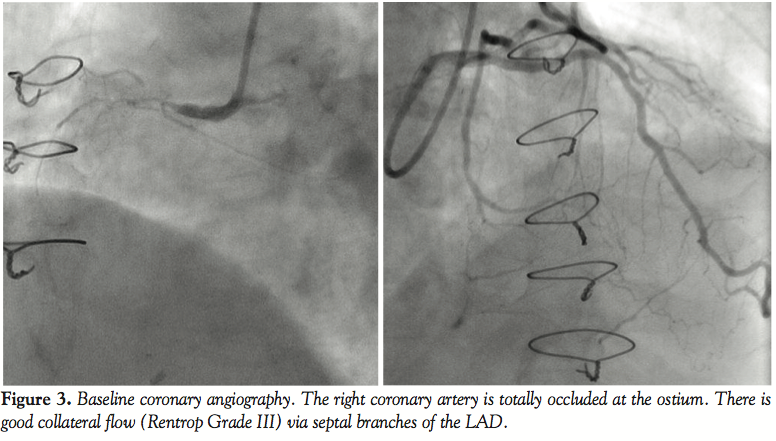

On coronary angiography (Figure 3), the RCA was totally occluded at its ostium. Selective catheterization of the left coronary artery showed retrograde filling of the RCA through a large collateral vessel (Rentrop grade III) arising from a septal branch of the left anterior descending coronary artery (LAD). Left ventriculography showed normal wall motion.